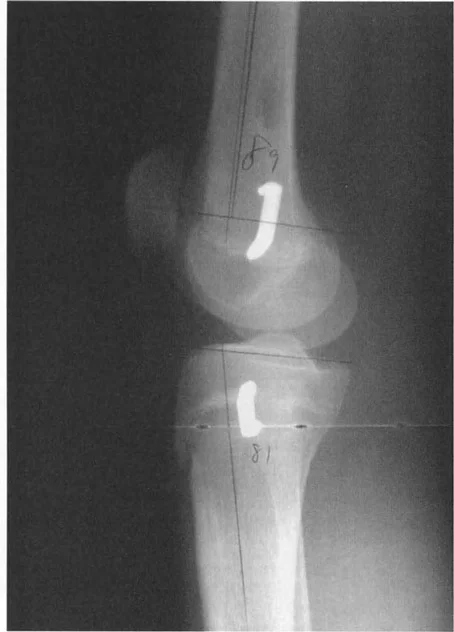

متى تتم إزالة دبابيس تثبيت الصفيحة المشاشية

في بعض الحالات، قد يختار الجراح إجراء تثبيت الصفيحة المشاشية في سن مبكرة مع خطة لإزالة الدبابيس بمجرد تحقيق التصحيح المطلوب، مما يسمح باستئناف النمو الطولي. يمكن استخدام طريقة المضاعف للتنبؤ بتوقيت إزالة الدبابيس.

- الصيغة: المضاعف عند وقت إزالة الدبوس (M2) = L1 × M1 / (L1 + E/K)

- L1 = طول العظم الحالي.

- M1 = المضاعف الحالي.